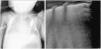

A two-month infant was admitted due to suspected infection. Four hours after packed platelets transfusion, and with no prior ventilatory support, the patient suffered progressive worsening with tachypnea and labored breathing that required noninvasive ventilatory support (maximum PIP 15/PEEP 7 and FiO2 70%). At that time, pulmonary ultrasound revealed characteristics consistent with acute respiratory distress syndrome, presenting bilateral coalescent B lines (asterisk) without aeration zones and a thickened pleura (>0.5mm), associated to subpleural condensations (Fig. 1). No lung pattern changes were evidenced with diuretics, and intubation was decided (volume control mode presenting tidal volume 6ml/kg with PIP 35 cmH2O, PEEP 14 cmH2O, respiratory frequency 35rpm, and FiO2 100%) – the condition being interpreted as representing transfusion-related acute lung injury (Fig. 2).